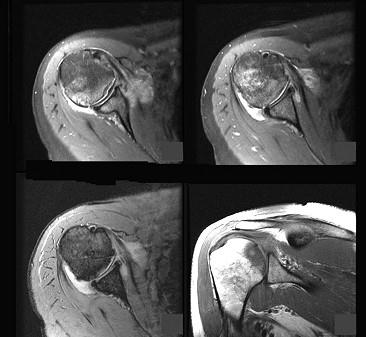

女,34岁,肩部疼痛,结合图像,最可能的诊断是 ( )A、肱骨头缺血坏死B、痛风C、类风湿关节炎D、肩关节退行性变E、未见异常

问题 女,34岁,肩部疼痛,结合图像,最可能的诊断是 ( )

选项 A、肱骨头缺血坏死 B、痛风 C、类风湿关节炎 D、肩关节退行性变 E、未见异常

答案 A